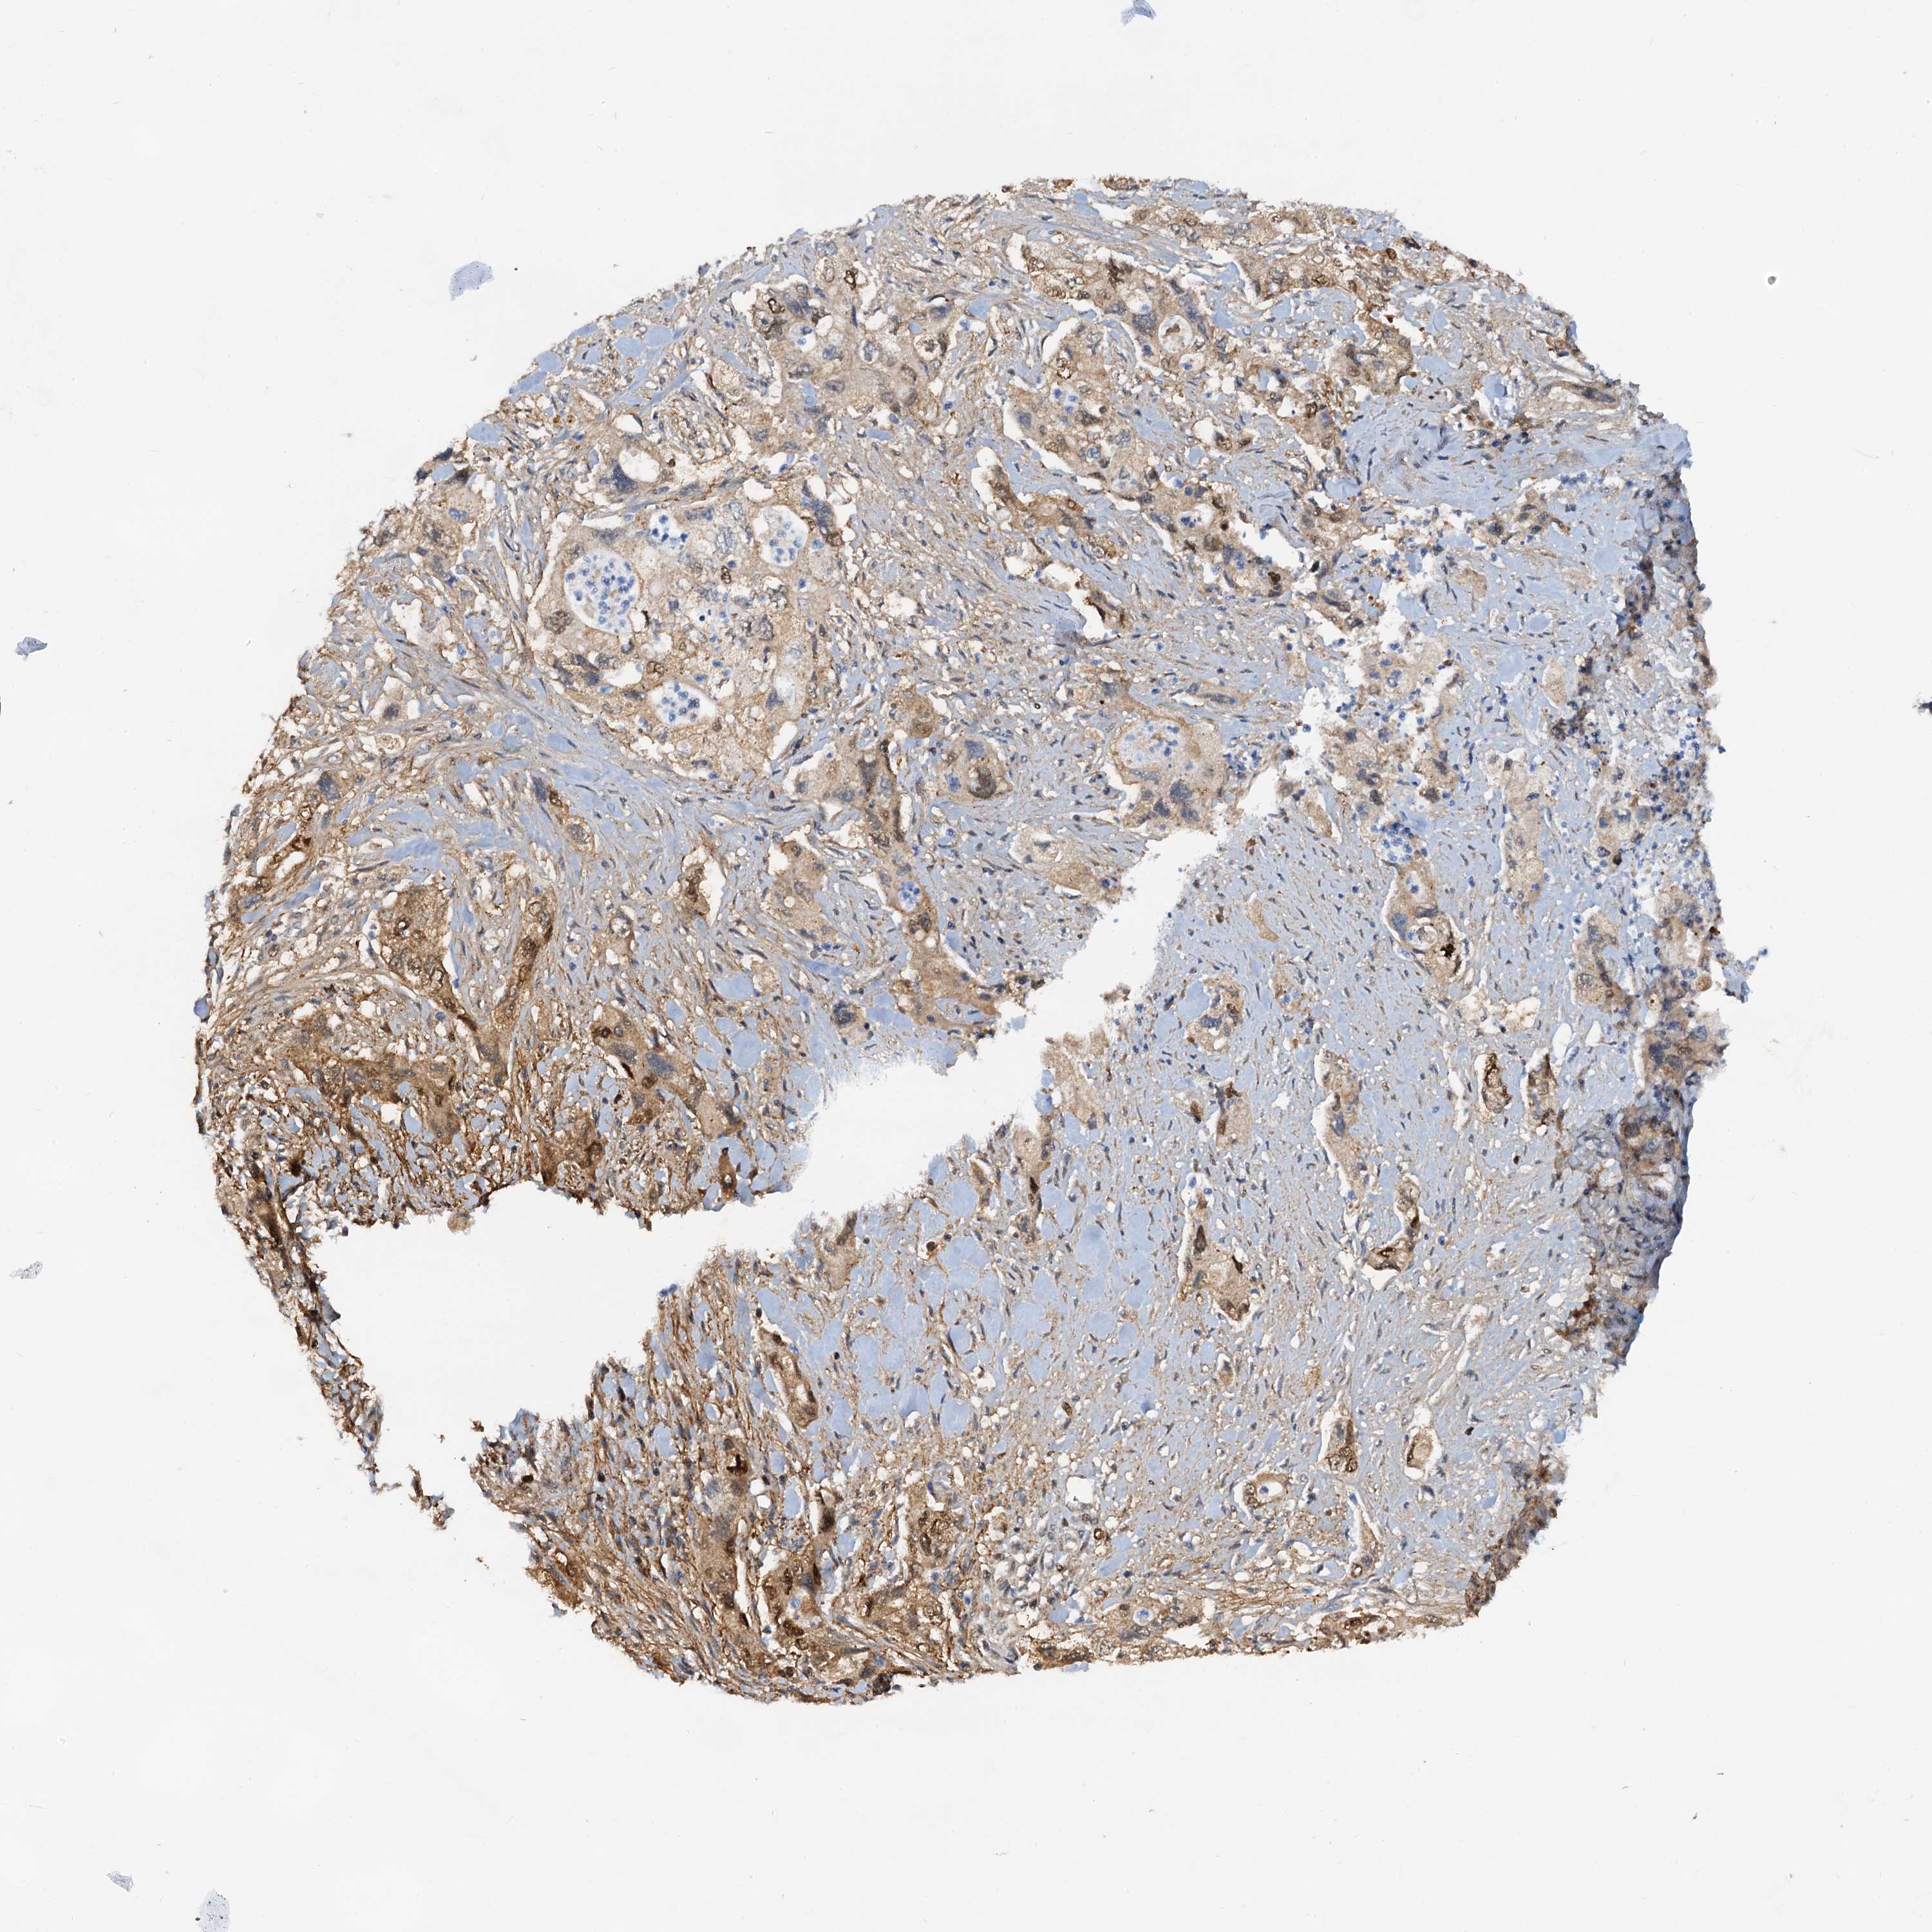

PANCREATIC CANCER - Protein expressioni

A mouse-over function shows sample information and annotation data. Click on an image to view it in a full screen mode. Samples can be filtered based on level of antibody staining by selecting one or several of the following categories: high, medium, low and not detected. The assay and annotation is described here.

Note that samples used for immunohistochemistry by the Human Protein Atlas do not correspond to samples in the TCGA dataset.

Antibody stainingi

Antibody staining in the annotated cell types in the current human tissue is reported as not detected, low, medium, or high, based on conventional immunohistochemistry profiling in selected tissues. This score is based on the combination of the staining intensity and fraction of stained cells.

Each image is clickable and will lead to virtual microscopy that enables deeper exploration of all samples and also displays staining intensity scores, fraction scores and subcellular localization as well as patient and tissue information for each sample.

Antibody HPA038672

Antibody HPA038673

Antibody CAB034319

Staining

High

Medium

Low

Not detected

Intensity

Strong

Moderate

Weak

Negative

Quantity

>75%

75%-25%

<25%

None

Location

Nuclear

Cytoplasmic/membranous

Cytoplasmic/membranous,nuclear

Adenocarcinoma, NOS